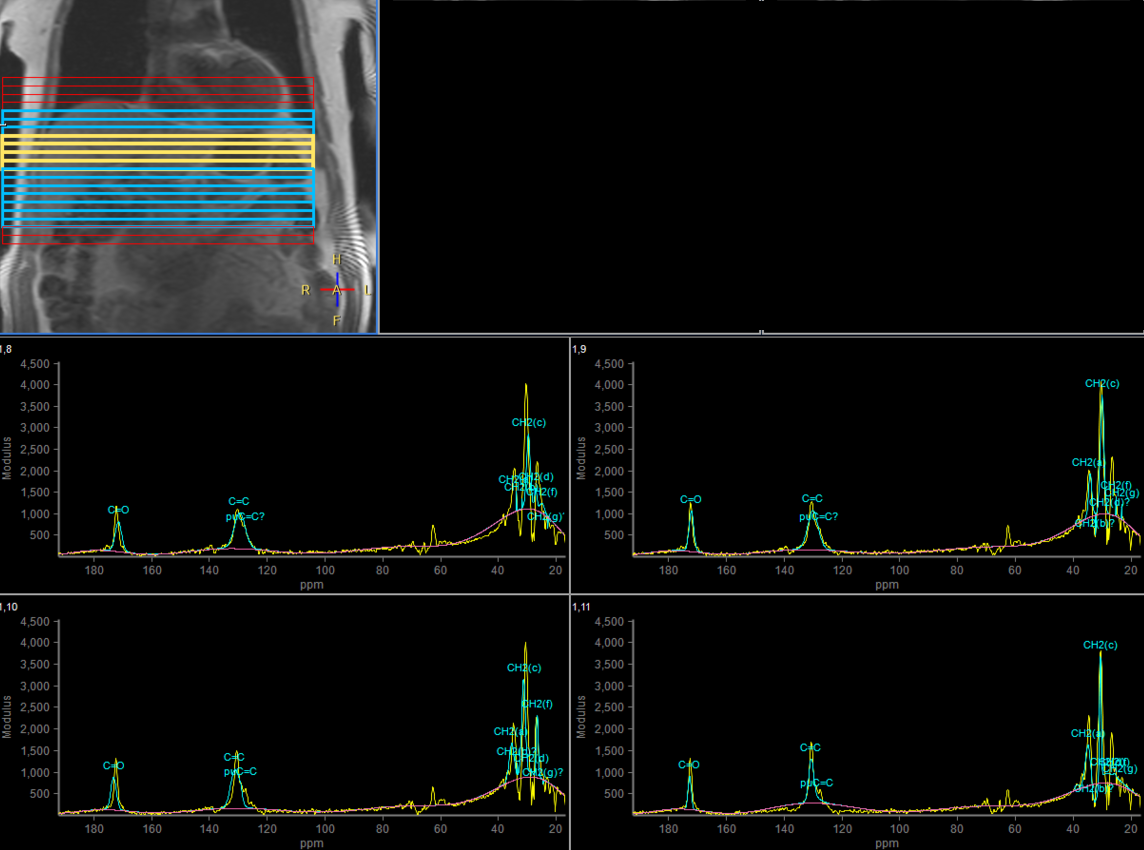

Multi Nuclei - Liver imaging (13C)

Make multi-nuclei imaging and spectroscopy become part of your clinical operations via a seamless integrated workflow for multi-nuclei image acquisition, spectroscopy, reconstruction, and viewing. The nucleus is just a scan parameter like any other sequence parameter. A single ExamCard can be used to run both proton and non-proton imaging. Reconstruction and viewing of non-proton images or spectra, as well as the process for sending the data to PACS is fully integrated, so workflow does not differ from proton imaging. The transmit-receive 13C flex coil, with a 14 cm diameter, is immediately recognized by the ExamCard interface. Improved SNR and simplified spectra* are achieved by combining body coil decoupling with the transmit-receive surface coils.

*Compared to non-decoupled spectroscopy results.Results from case studies are not predictive of results in other cases. Results in other cases may vary.